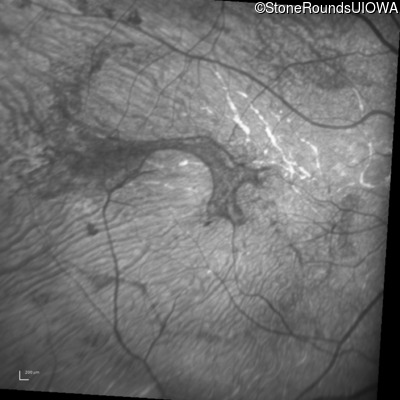

This 30 year old woman has had poor vision in her right eye for her entire life and first noticed decreased vision in dim light and constricted fields in her left eye in middle school. She had surgery in infancy for "short gut syndrome" and had liver transplantation at age 3. She also has a history of pulmonary stenosis, scoliosis, and ataxia.

| Alagille Syndrome | JAG1 | Gly193del1tatG | AD |